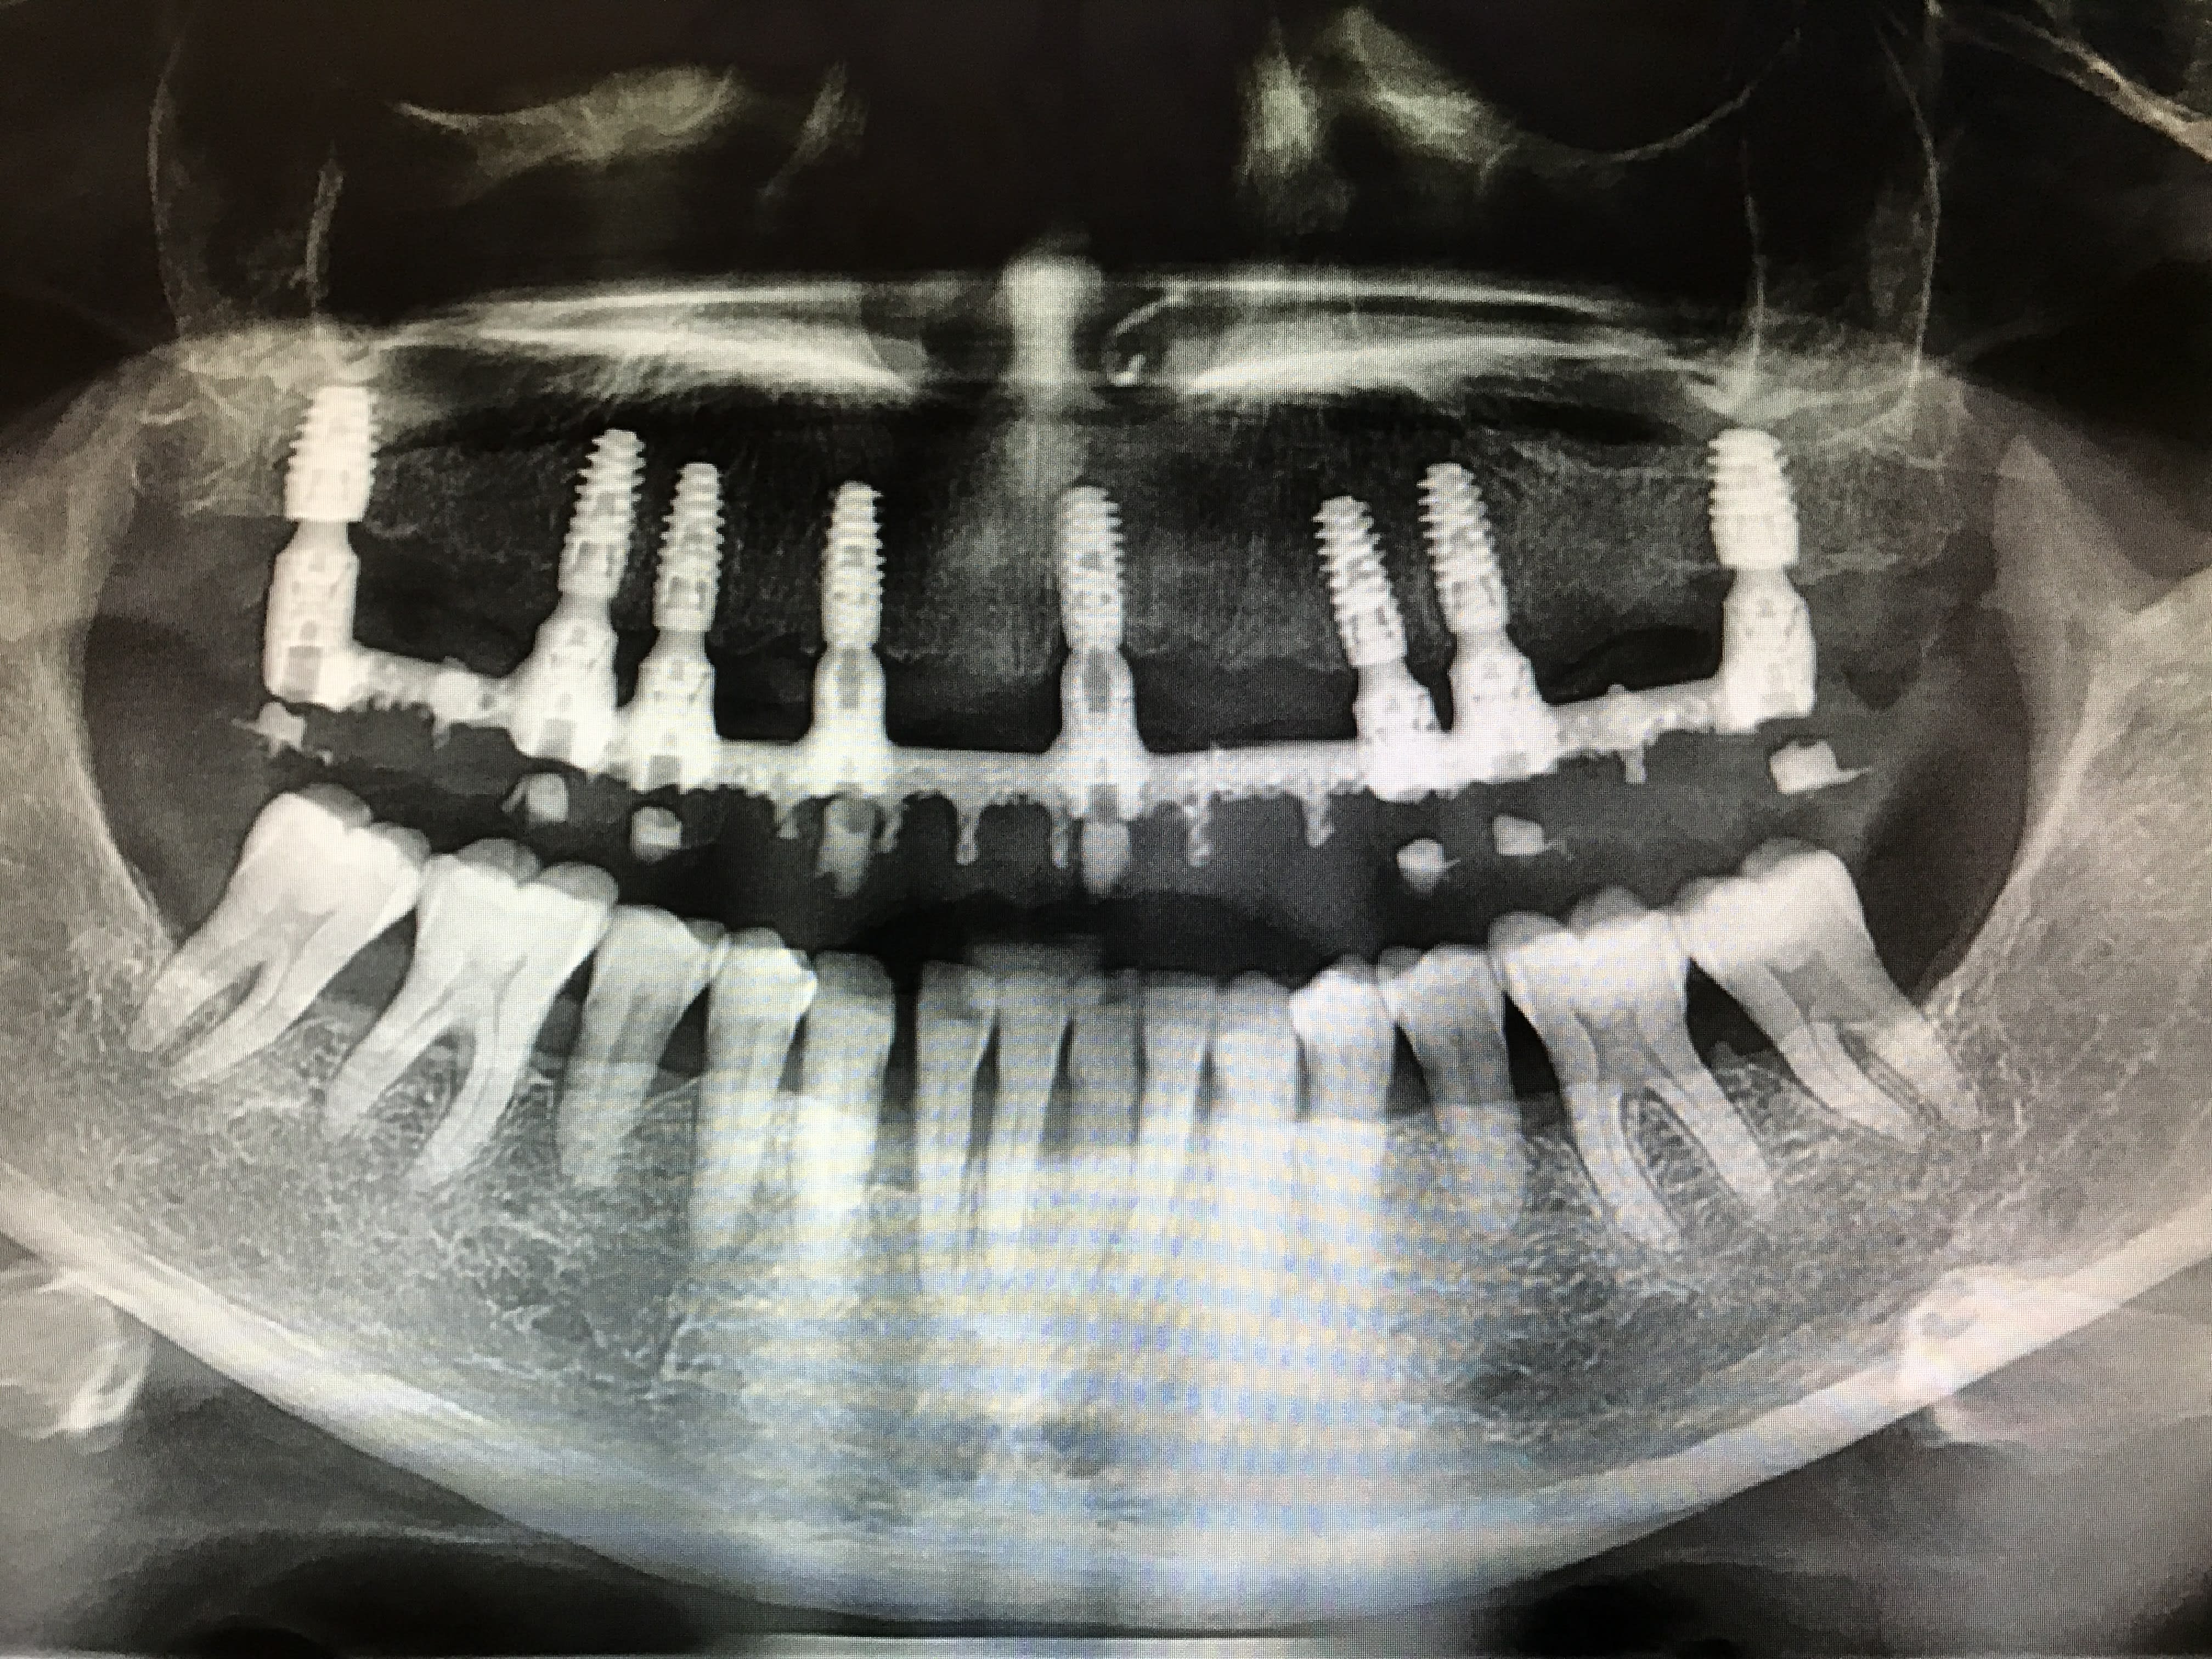

C'est mon premier cas de mise en charge immédiate.

Patient de 82 ans, sous préviscan, INR autour de 2,5 toute l'année.

Nous avons décidé avec le patient de faire une arcade courte (16-26) sur 6 implants. Une fois le haut validé, nous ferons le bridge 32-42 sur 2 implants + le remplacement de la 36.La 48 est à extraire et la 38 à voir.

J'ai fait une simulation des implants avec CBCT. J'ai prévu utiliser Anthogyr axiom PX: 10mm de long, 4,6mm en postérieur et les 4 autres en 4mm.

Lors de la pose, l'assistante s'est trompé d'implant (et avec le stress je ne l'ai pas vérifié) pour le 24 (4,6 au lieu de 4mm). Je m'en suis rendu compte au moment de la 16 (plus de 4,6 en PX..) j'ai mis un 4,6 mais en REG, avec un blocage à 25N.

Ensuite la pose des piliers MU, droit standards sauf pour la 13 où j'ai du en poser à 20 degrés angulé pour suivre la crête antérieure bien résorbée.